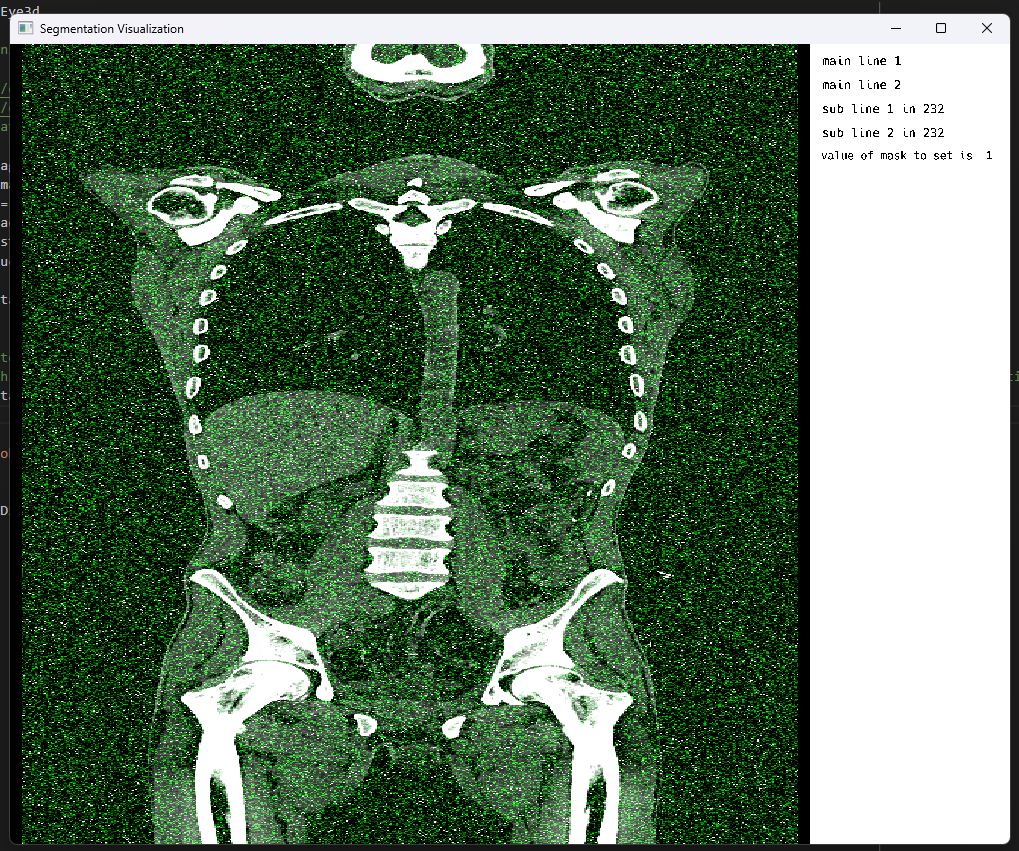

Eventually, with ever so increasing number of attempts and a few hurdles along the way, one of which particularly stood out since it marked our first step towards a good direction:

Challenges in rendering

At last, an appealing result hit our sight.

Final result

Note: The image borders are intentional to emphasize the size of the visualizer which is currently defaulted to a certain width and height.